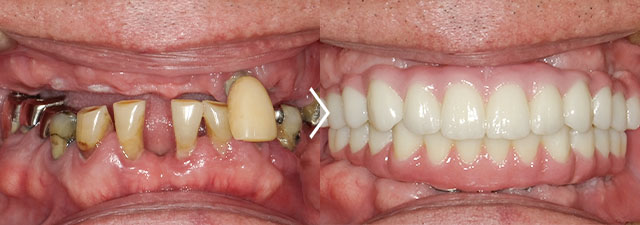

上顎をオールオン6、下顎がオールオン4で治療しました。

<上顎>オールオン6 3,100,000円(税抜)、インプラント二次手術10,000円(税抜)、サージカルステント作製30,000円(税抜)、仮歯(プロビジョナルレストレーション) アバットメント無10,000円(税抜)×6・アバットメント有30,000円(税抜)×6

<下顎>オールオン4 2,700,000円(税抜)、サージカルステント作製30,000円(税抜)、仮歯(プロビジョナルレストレーション) アバットメント無10,000円(税抜)×8・アバットメント有30,000円(税抜)×4

CT撮影料10,000円(税抜)